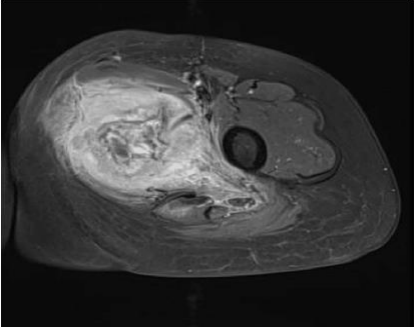

Magnetic resonance imaging (MRI) revealed a 4.7x7.2x9 cm irregular soft tissue mass in the left medial proximal thigh involving the adductor magnus muscle. The mass demonstrated intermediate and heterogeneous T2 signal intensity with an irregular peripheral T2 dark signal rim and intermediate T1 signal intensity. Additionally, the MRI showed extensive surrounding muscle and subcutaneous edema with a branch of the deep femoral artery coursing through the mass. Gadolinium-enhanced images revealed multilocular cystic areas surrounded by intense heterogeneous enhancement of the solid components. The mass demonstrated features concerning for malignancy [Figure 1, 2, 3, 4]. A fluorodeoxyglucose (F-18 FDG) PET scan demonstrated mildly hypermetabolic lymph nodes in the left inguinal region (suspected reactive) and a few small inflammatory nodules without FDG uptake in both lungs, but no evidence of distant metastasis [Figure 5].

FIGURE 2: Axial T1-weighted fat-saturated gadolinium-enhanced image Multilocular cystic areas in central part of lesion surrounded by intense heterogeneous enhancement of the solid elements

FIGURE 4: Coronal T2-weighted MR image Mass in adductor compartment of thigh with intermediate and heterogeneous signals